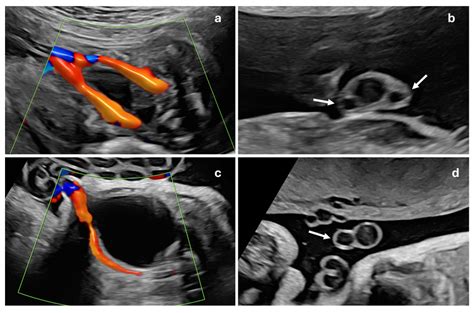

Most cases of one umbilical cord artery are detected during the routine mid-pregnancy anatomy scan, typically performed between 18 and 22 weeks of gestation. If an ultrasound technician or radiologist notices the absence of a second artery, they will often recommend a more comprehensive evaluation.

• Detailed Fetal Ultrasound: A more specialized scan to examine the baby’s heart, kidneys, spine, and other major organs to rule out structural defects.

Doppler Studies Evaluates blood flow resistance in the umbilical artery.